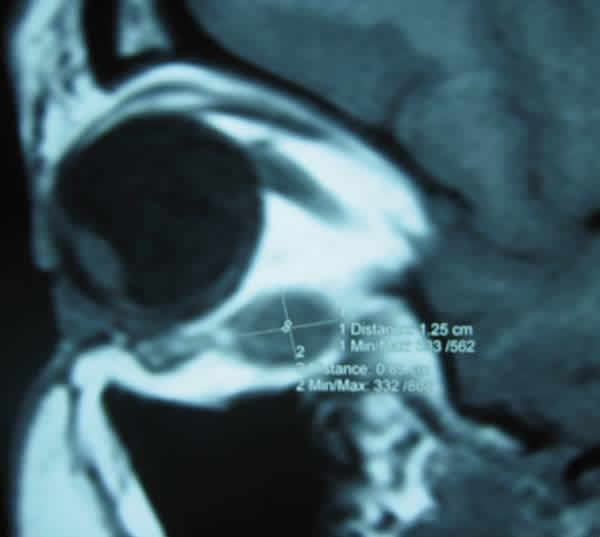

Aporta un estudio de RMN de órbitas en cortes axial, coronal y sagital con inyección de Gadolinio, objetivándose una masa intracónica en el cuadrante nasal y superior de la órbita izquierda en íntimo contacto con el nervio óptico y los músculos oblicuo mayor, recto superior y recto interno en sus 2/3 anteriores, con diámetros transverso, antero-posterior y vertical de 1,7x1,3x1,2 cm, considerándose el hemangioma intracónico la principal posibilidad diagnóstica (fig. 4).

Fig. 4: A: RMN sagital SE T1 con gadolinio (Gd-DPTA). B: RNM coronal SE T1. Masa intracónica en el cuadrante nasal y superior de la órbita izquierda relacionada con nervio óptico y músculos oblicuo mayor, recto superior y recto interno, de 1,7x1,3x1,2 cm.